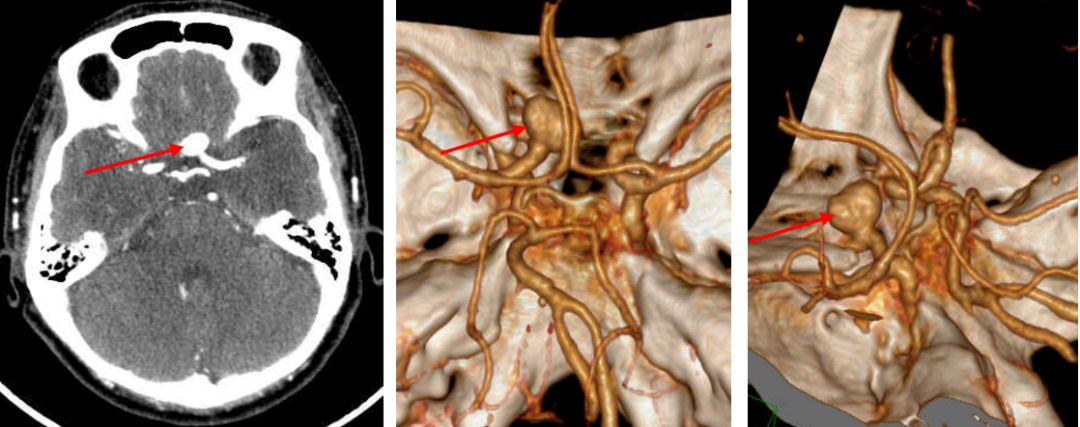

1. 术前CTA: